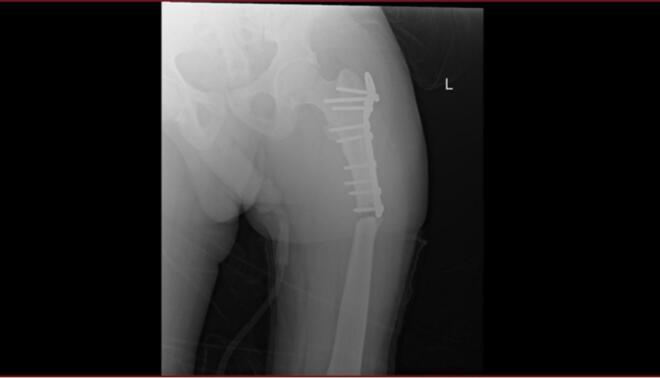

We present a 45-year-old male with adult-onset autosomal dominant osteopetrosis who sustained bilateral subtrochanteric femoral fractures-first on the right side, then on the left two years later. Both fractures were managed with intramedullary nailing (IMN). The procedures were technically demanding due to the sclerotic bone and canal obliteration, requiring sequential drilling and reaming with irrigation to prevent thermal necrosis. Both fractures healed without complications, with radiographic union at 9 months and early mobilization.

我们报告一名45岁成年男性,患常染色体显性遗传性成人骨质石化症,双侧股骨转子下骨折——右侧先发生骨折,两年后左侧发生骨折。两处骨折均采用髓内钉固定(IMN)治疗。由于骨质硬化和髓腔闭塞,手术操作技术要求高,需要依次钻孔、扩髓并冲洗以防止热坏死。两处骨折均愈合且无并发症,9个月时影像学显示骨折愈合,并可早期活动。